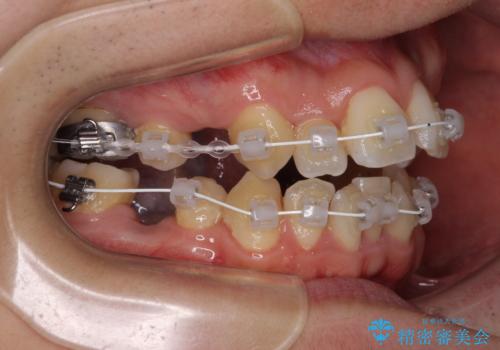

重なり合って磨きにくい前歯 ワイヤー装置での抜歯矯正

- 前歯の著しいデコボコを気にして来院された患者様です。

上顎の左右側切歯(前から2番目)が裏側に隠れいてる状態で、咬み合わせや清掃性に大きな問題が認められました。

叢生が著しいため、上下左右の小臼歯4本を抜去し、目立たないワイヤー装置にて矯正治療を行うこととしました。

下顎の歯列全体が右側にずれているため、右下のみ第二小臼歯を抜歯し、上顎は補助装置を使用して、極力上下の正中を合う位置にて咬み合わせを改善するようにしました。